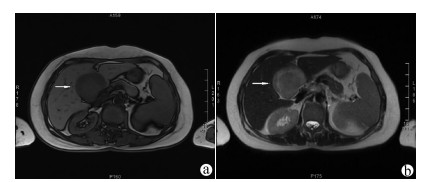

肝细胞癌合并胃肠间质瘤1例报告

杨旭, 史政荣

2021, 37(8): 1909-1910. DOI: 10.3969/j.issn.1001-5256.2021.08.033

摘要(897) HTML (273) PDF (2171KB)(69)

摘要: